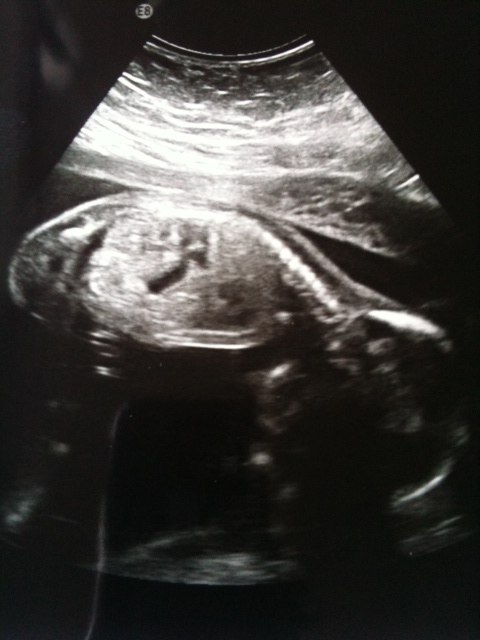

En PIGE, som ligger i maven og hygger sig, hun var så aktiv at de havde svært ved at scanne hende, og så ligger hun med hovedet godt begravet så det var svært at scanne det, men det hele gik godt og der er ingen tegn på misdannelser, så vi er super glade, og fejrede det ved at tage i IKEA og købe det pudslebord vi ville have